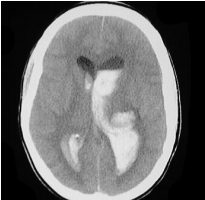

・クモ膜下出血:脳脊髄液の領域に出血が起こり、発症後数分で高吸収域として検出される。脳動脈瘤破裂が8割程を占め、原因として最多であるがその他外傷や腫瘍、動静脈奇形なども原因となりうる。

クモ膜下出血のCT https://www.uic.edu/com/ferne/pdf/acep_2005_peds/perron_ich_acep_2005_peds_course.pdf